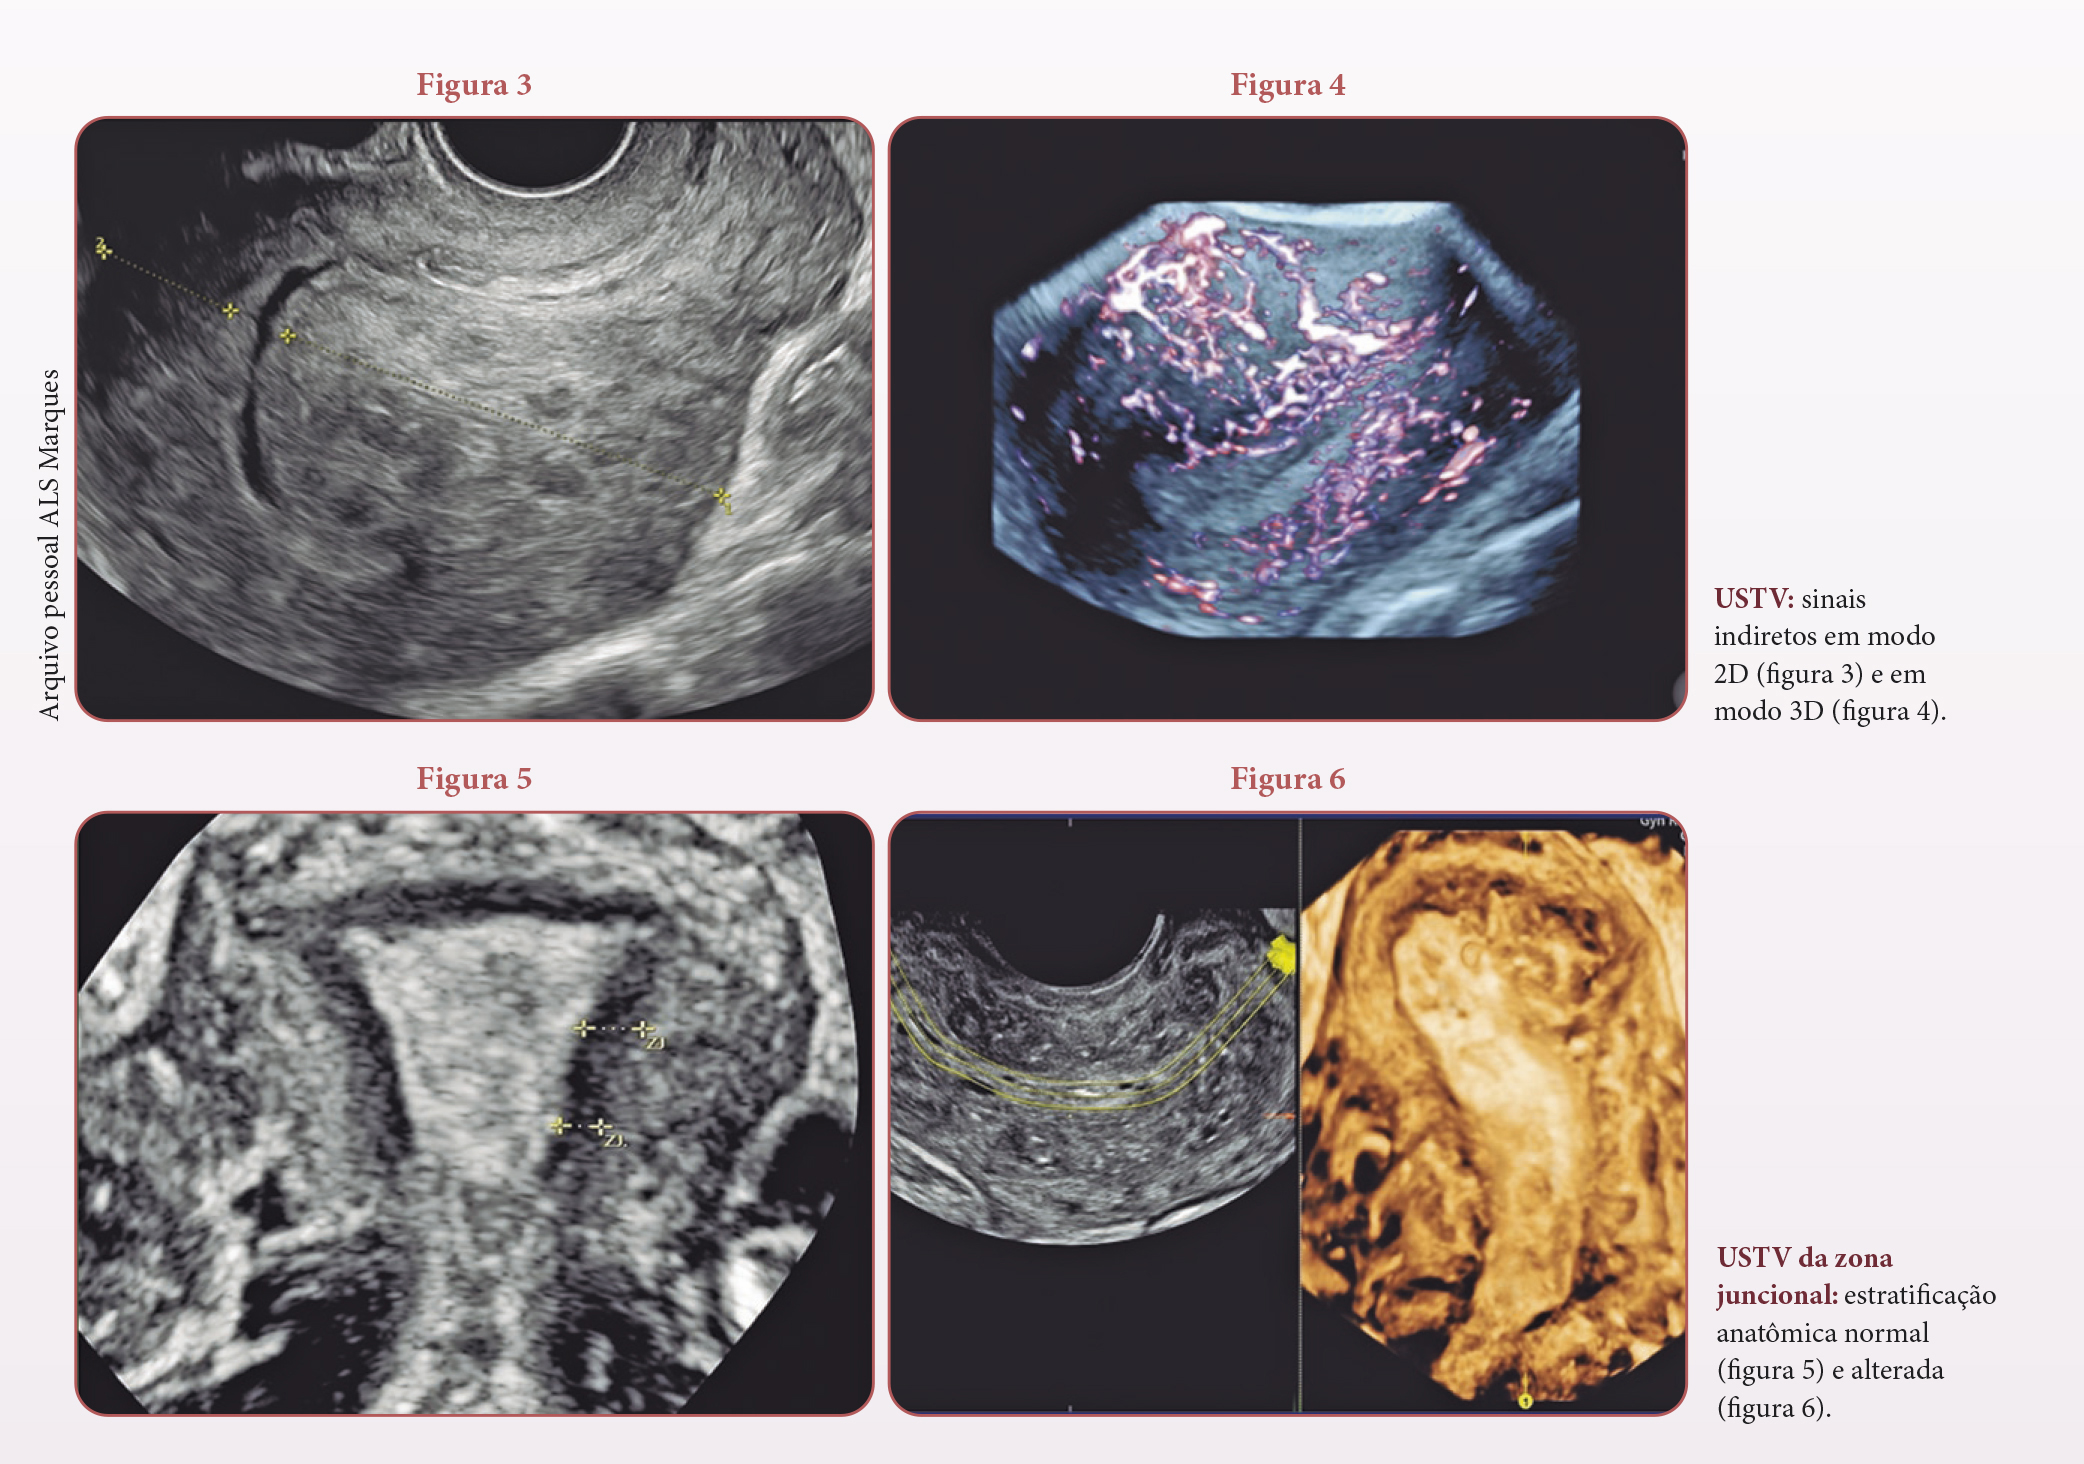

A ultrassonografia transvaginal, tanto na modalidade 2D quanto na 3D, é amplamente utilizada para avaliar esses marcadores de acordo com os critérios Musa, bem definidos e padronizados para o diagnóstico da condição. Critérios diretos (figuras 1 e 2) incluem a presença de tecido endometrial ectópico dentro do miométrio, de cistos subendometriais e intramiometriais, de ilhotas hiperecogênicas e de estrias lineares hipoecoicas. Já os indiretos (figuras 3 e 4) observam mudanças estruturais avançadas, como útero globoso, assimetria das paredes uterinas e aumento da vascularização, tipicamente translesional e difusa no útero.

Estudos apontam que achados como estrias lineares hipoecoicas, espessamento da zona juncional e alterações vasculares detectadas pelo Doppler colorido são fundamentais para avaliar o comprometimento uterino. A sensibilidade e a especificidade da ultrassonografia transvaginal em modo 3D mostram-se significativamente superiores às técnicas bidimensionais, alcançando até 85% de sensibilidade e 82% de precisão na detecção de alterações específicas relacionadas à interface endométrio-miométrio.